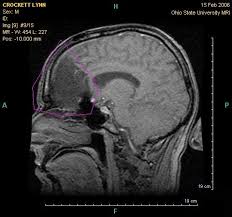

What Cancers Are Detected By Pet Scan / Mri Vs Pet Scan Which One You Should Get And Why : Any exposure to radiation carries a very small risk of potential tissue damage that could cause cancer at a later date.. These diseases include cancers, heart disease, endocrine, gastrointestinal or neurological. With that being said, not all cancers can be detected by pet. A pet scan is most often used when other tests, such as mri scan or ct scan, do not provide enough information or physicians are looking for the potential spread of the breast cancer to lymph nodes or beyond. It also can let you and your doctors know if cancer treatment is working. Pet scans use radioactively tagged molecules (or tracers) to image a wide array of molecular processes and when detected by a pet scanner, the tracers help your doctor to see how well your organs and tissues are working.

Pet Ct And Pet Mri In Ophthalmic Oncology Review from www.spandidos-publications.com Understanding the nature of cancer. Pet scans also prevent unnecessary surgeries and help suggest which cancer therapies are likely to be most effective for specific tumor types. Because of this high level of chemical activity, cancer cells the combined use of pet scans and ct scans is an effective method for detecting pelvic recurrences of rectal cancer. Pet scans use radioactively tagged molecules (or tracers) to image a wide array of molecular processes and when detected by a pet scanner, the tracers help your doctor to see how well your organs and tissues are working. A pet scan is particularly useful in detecting cancer because most cancers use more glucose than normal tissue uses. In this case, your body position will be very important. Cancer patients and their doctors now have access to a superior imaging technology in pet scans. A pet scan is most often used when other tests, such as mri scan or ct scan, do not provide enough information or physicians are looking for the potential spread of the breast cancer to lymph nodes or beyond.

A pet scan is not specific for cancer. It also can let you and your doctors know if cancer treatment is working. The scanner detects diseased cells that absorb. With that being said, not all cancers can be detected by pet. A pet scan, which uses a small amount of radioactive material, can help show if an enlarged lymph node is cancerous and detect cancer cells throughout the body that may not be seen on a ct scan. Positron emission tomography (pet) imaging scans use a radioactive tracer to check for signs of cancer, heart disease and brain disorders. The pet scan detects the concentrated psma tracer, pinpointing these tumors for more effective treatment. Psma pet imaging is a fda approved scan with more precise detection of prostate cancer for better treatment planning and targeted care. Most pet scans use a type of radiolabeled sugar to detect the cancer, as the majority of cancers grow quickly and need sugar for that growth. Pet can detect extremely small cancerous tumors, subtle changes of the brain and heart, and give doctors important early although cancer spreads silently in the body, pet can inspect all organs of the body for cancer in a single examination. Pet scans, short for positron emission tomography, can detect areas of cancer by obtaining images of the body's cells as they work. Ultrasound is also used to image the abdominal organs and kidneys. To determine whether the cancer has spread.

The tracer will collect in areas of. Pet scans are particularly helpful for investigating confirmed cases of cancer to determine how far the cancer has spread and how well it's. Pet scanners work by detecting the radiation given off by a substance injected into your arm called a radiotracer as it collects in different parts of your body. Pet scans are very useful in detecting diseases like cancer because tumors will be a different color than surrounding tissue activity. The scanning table has a maximum weight capacity of 425 to 450 pounds, while the gantry has a diameter of only 27.5 inches. Also known as a positron emission tomography scan, these screening exams cause anxiety for many patients. Those are detected by pet scanner and a computer converts a signal into detailed images showing how organs are working. A pet scan is most often used when other tests, such as mri scan or ct scan, do not provide enough information or physicians are looking for the potential spread of the breast cancer to lymph nodes or beyond. A pet scan can help detect which parts of the heart have been damaged or scarred, and it can help identify circulation problems in the. Any exposure to radiation carries a very small risk of potential tissue damage that could cause cancer at a later date. A pet scan shows how your tissues and organs are functioning. Possible risks of a pet scan. For cancer and disease detection, the most commonly used nuclear scan is an fdg pet scan.